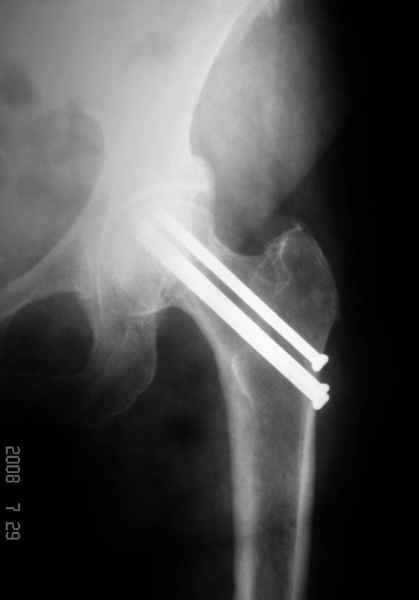

77 летняя больная направлена в нашу клинику на дальнейшее лечение. Из истории, травму получила в сентябре 2007 года и по поводу перелома шейки бедра больная была проперирована тремя каннюлированными шурупами с явным нарушением технологии установки шурупов. Внизу вместо одного шурупа имеется два, что привело к стрессу латерального кортекса. Через месяц по поводу ятрогенного подвертельного перелома сделана фиксация длинной Гамма 3. Установлен без проксимальной блокировки? (set screw). В данный момент имеется несостоятельность конструкции и ложный сустав. Передвигается с помошью костылей, конечность укорочена на 2 см. Какие будут рекомендации?Djoldas Kuldjanov, MDDepartment of Orthopedic SurgerySt. Louis University Medical Center